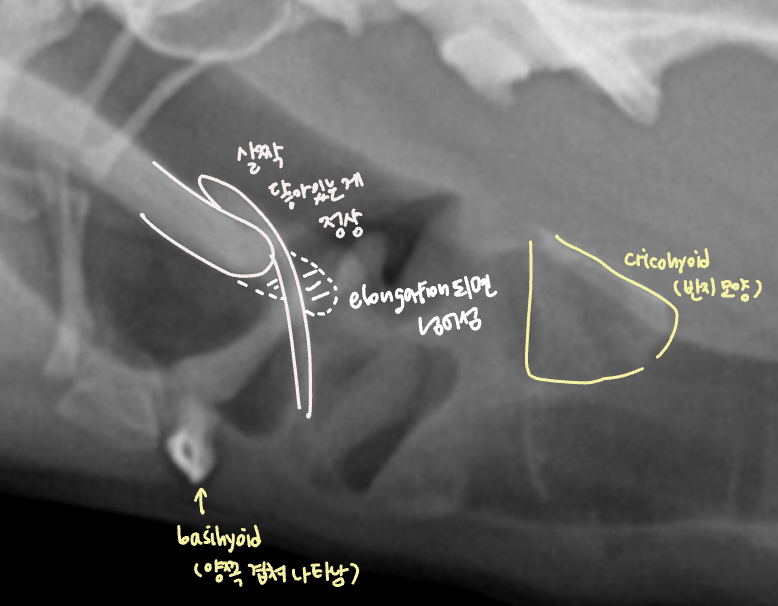

Brachycephalic syndrome

| Brachycephalic syndrome |

|---|

| ๋จ๋์ข

- English bulldog, Pug, Pekingese, French Bulldog, Bonston Terrier.. ์์ธ - Skull์ base๊ฐ ์ ์ ์ ์ผ๋ก ์งง์ - ๊ตฌ์กฐ์ ์ผ๋ก ์ผ๊ตด์ด ์งง์ ๊ตฌ์กฐ๊ฐ ๊ณผ๋ฐ๋จ Complex - stenotic nares (๋น๊ณตํ์ฐฉ) - soft palate edema & elongation (์ฐ๊ตฌ๊ฐ๋ ธ์ฅ) - laryngeal edema, saccules, collapase, paralysis - (dynamic) pharyngeal collapse GI complication - Hiatal hernia - gastroesophageal reflux (์ญ๋ฅ์ฑ ์๋์ผ) |